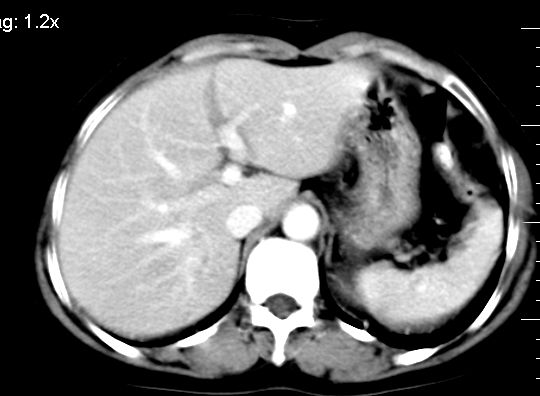

ct表现:

肝大小形态未见异常,肝内外胆管无扩张,肝s8段见一动脉期明显血管样强化结节,门脉期呈高密度,延迟期呈等密度,胆囊不大,增强扫描见胆囊及胆囊颈管壁增厚,有强化。

双肾灌注良好,代谢增快,动脉期肾盂见造影剂,左肾下极背侧见一略低密度病灶,延迟期见似不强化囊肿,双侧肾上腺未见异常。

胰腺及脾未见异常。肾门水平腹膜后见小淋巴结。腹腔未见积液征象。

1、胆囊炎(轻度)。

2、肝s8段结节,考虑小血管瘤。

3、左肾下极低密度灶,考虑囊肿可能性大,建议随访,除外小肾癌(无强化可以基本除外)。

4、目前ct表现尚不能解释患者上腹部疼痛,建议上消造影检查,除外胃炎等疾患。